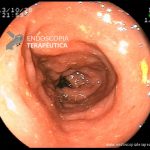

- Doença de Crohn em remissão – cicatriz